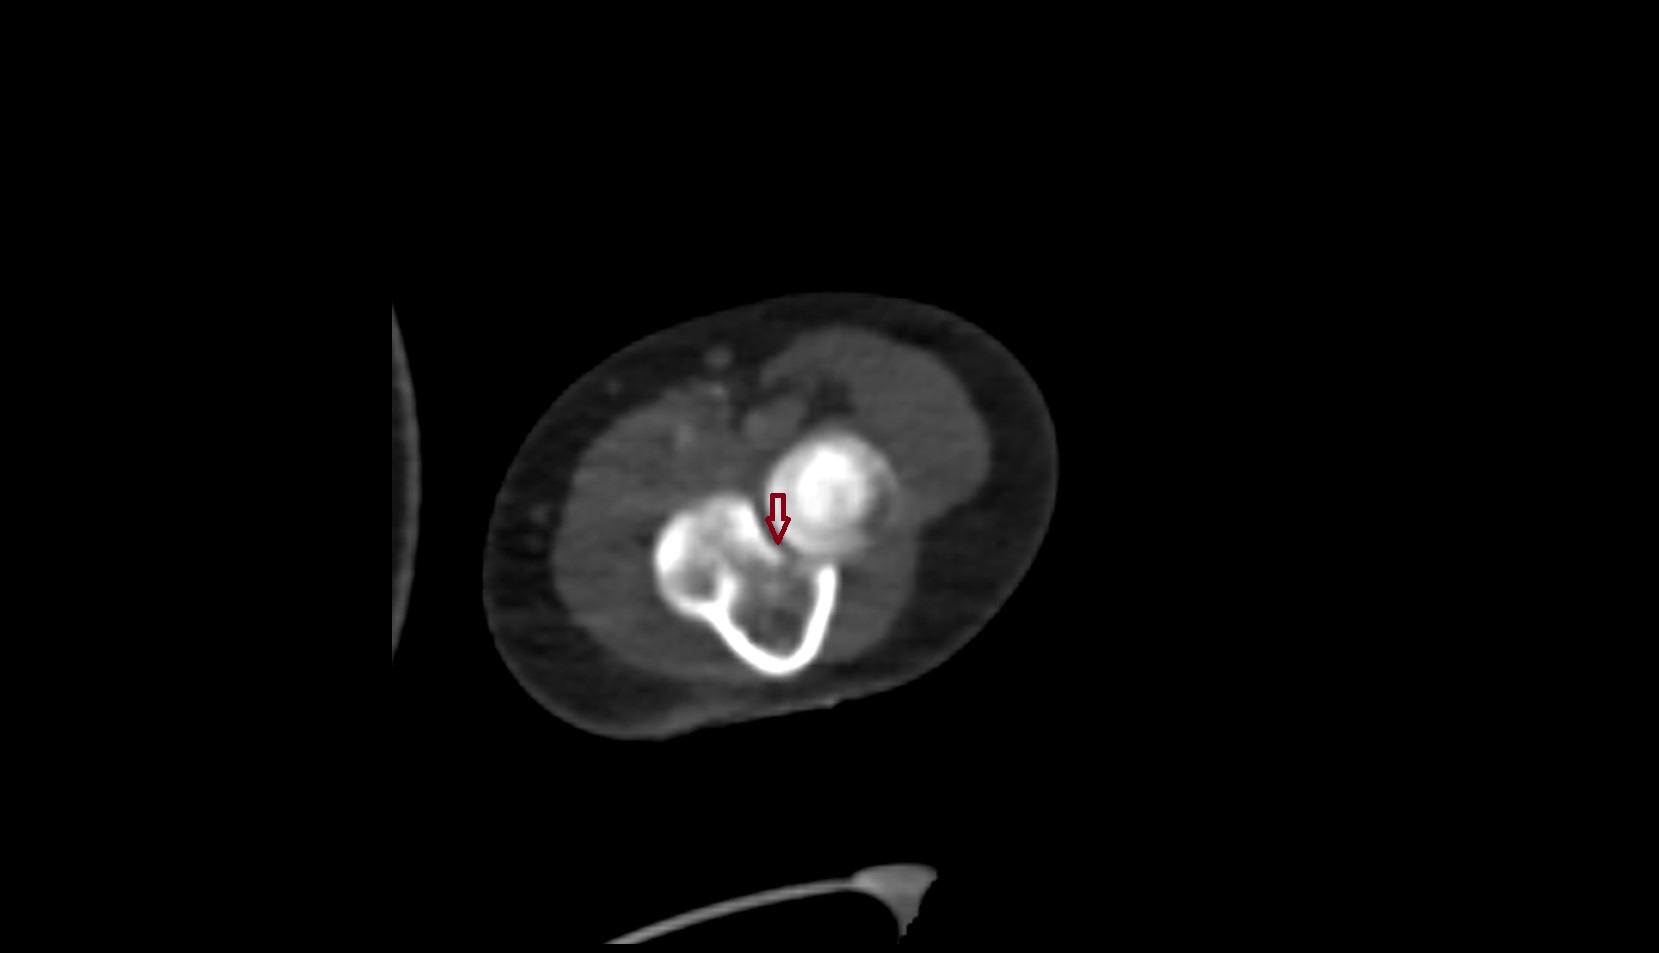

- Elbow joint